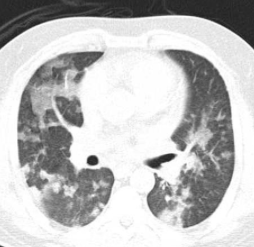

Multifocal peripheral consolidation/ground glass

COP

A

1. Cryptogenic organising pneumonia (more lower lobe. Subpleural sparing)

2. Eosinophilic pneumonia (upper lobe more than lower. Can look like pulmonary oedema)

Eosinphilic

Ground glass opacification

1. Pulmonary oedema

2. Pulmonary haemorrhage

3. Atypical infection (PCP, CMV)

4. ARDS

ARDs vs pulmonary oedema: normal size heart and no pleural effusion in ARDS